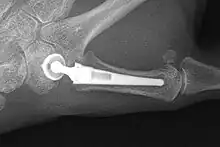

Joint Replacement

The joint can be replaced with artificial material. An artificial joint is also referred to as a prosthesis. Prostheses are more problematic at the trapeziometacarpal joint compared joints like the knee or the hips.

[27]Prostheses come in many varieties, such as spacers or resurfacing prostheses.

It’s not clear within the current literature that a prosthesis has any advantage over trapeziectomy.[27]

Overall, joint replacements are related to long-term complications such as subluxation, fractures, synovitis (due to the material used) and nerve damaging.[35] In many cases revision surgery is needed to either remove or repair the prosthesis. Also note that usage of a joint replacement is heavy in costs.

The quality of the prostheses is improving and there is reason to believe this will have a positive effect on outcome in the years to follow.[27]